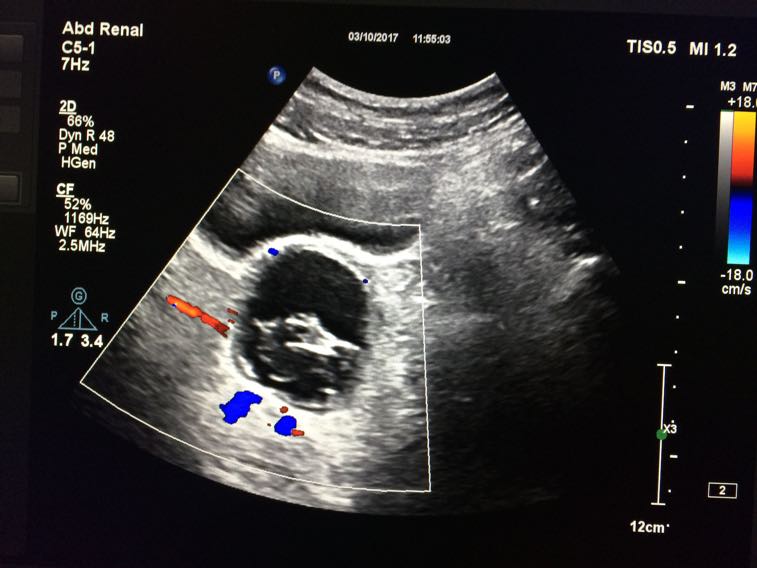

卵巢囊肿

月经前一天做彩超示:右侧卵巢囊肿大小约为56×44mm ,乳腺增生。症状:月经推后十天,量少,色暗黑红,质稠,夹血块多。纳可眠可,大便不成型,小便正常。无痛经,无乳房胀痛,无腰酸,不怕冷。舌苔白腻,脉?囊肿经验方或者常用中药?